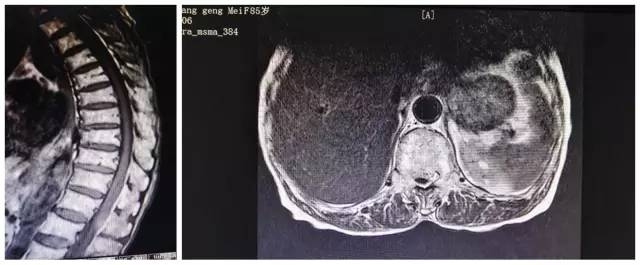

家人曾聽說惠州市第三人民醫(yī)院骨科醫(yī)術精湛,為求進一步治療,連夜把奶奶送往三院東院區(qū)科醫(yī)學中心頸肩腰腿痛科,科室醫(yī)師高度重視,發(fā)起骨科醫(yī)學中心內(nèi)部多??坡?lián)合診療機制,經(jīng)于脊柱外科會診并在院內(nèi)相關部門協(xié)調(diào)下申請了急診核磁共振等檢查,結(jié)果顯示“胸腰段椎管內(nèi)占位(性質(zhì)待查)”。中心主任武明鑫博士查看病人及各項資料后基本判定為“胸腰段的椎管內(nèi)硬膜外出血導致癱瘓”。

病人MRl(核磁共振成像)檢查片

由于椎管內(nèi)占位壓迫神經(jīng)并已導致癱瘓,需盡早手術減壓,不然可能會導致永久癱瘓,但因奶奶年紀大,麻醉等方面風險高,家屬一度想放棄手術。武明鑫博士立即組織醫(yī)生們進行了全面的術前討論,制定周密的手術方案,要求椎管內(nèi)占位病灶應盡快清除,解除脊髓壓迫。